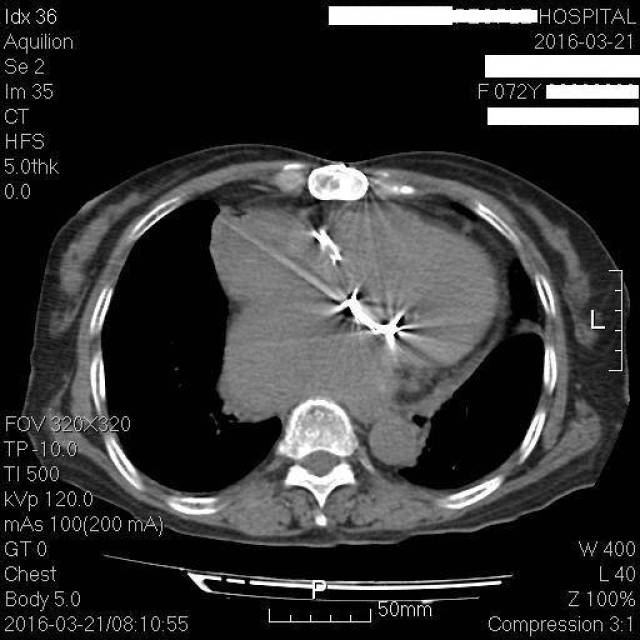

中年女性,风心病二尖瓣,主动脉瓣置换术后,纵隔新生物是什么?

心外科的医师看了胸部ct,这机械瓣,这伪影像闪动的光芒,可惜照不亮她